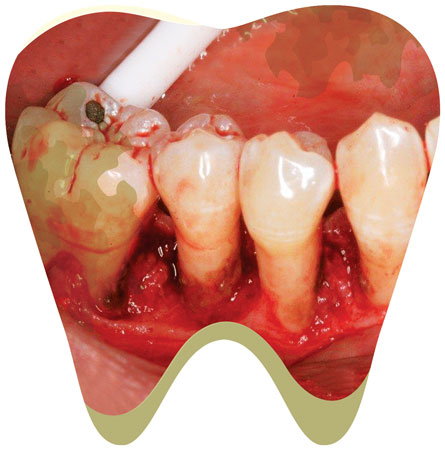

When describing calculus attachment to my patients, I like to use the analogy that the calculus attaches to the tooth like a barnacle attaches to a boat. Barnacles produce cement that is released through the tips of their antennules to attach themselves (Grunbaum, 2010). Calculus attaches by mechanically interlocking to the crystals of the tooth, using the acquired pellicle (Roberts-Harry EA, 2000 ;28). Burnished calculus is a subgingival deposit that has had its outermost layer shaved off - but not fully removed - so that the surface is smooth yet still attached to the tooth surface, contributing to disease (Pattison, 2011). When clinicians do not recognize or remove burnished calculus, they are practicing supervised neglect. One wouldn’t “plane away” a barnacle off a boat, nor should you “shave away” calculus from a tooth; in either scenario, you will leave the source of the irritant.

These areas of burnished deposits will contribute to persistent gingival inflammation and bleeding, in addition to providing a constant food source for more bacteria. This vicious cycle will continue until you completely remove all calculus. We set our patients up for failure when, every six months, we tell them to brush and floss to reduce recurrent bleeding while we leave burnished deposits subgingivally.

Recognizing burnished calculus can be challenging, even for the skilled clinician. Isolated areas of tissue color change, slight inflammation, or bleeding upon probing in a patient who effectively brushes and flosses regularly may be signs of areas where burnished calculus is present. These areas will not heal until the irritant is removed. Change the way you examine your patient to determine if burnished deposits are present.

Leaving burnished calculus is more common than you may think. Research supports evidence demonstrating that blind root planing is effective only to 4 mm. Beyond 4 mm, 30% to 50% of the subgingival root surface is still covered with undetectable burnished calculus (Carroll, 2015). Burnished calculus is more likely to be found in areas on the root surface with developmental grooves, depressions, furcations, and at the cementoenamel junctions.